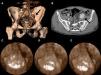

Tres meses después el paciente fue evaluado en consulta externa, refiriendo claudicación a muy larga distancia en dicha extremidad. En la exploración física presentaba by-pass pulsátil e ITB de 0,69; además se detectó una masa pulsátil por encima del ligamento inguinal izquierdo, por lo que se realizó una eco-doppler, objetivándose una imagen de aneurisma con flujo arterial en su interior de unos 4cm de diámetro a nivel del eje iliaco izquierdo. Se realizó angio-TAC, confirmándose la sospecha de pseudoaneurisma iliaco de 4,5cm de diámetro y morfología sacular situado en el extremo distal del stent de la iliaca común y con extensión hacia la iliaca externa (fig. 2A y 2B).

En quirófano y bajo anestesia locorregional, tras obtener una imagen angiográfica de la lesión (fig. 2C) se procedió a la implantación de dos stents recubiertos Wallgraft (90×50mm), para excluir el pseudoaneurisma (fig. 2D y 2E), mediante abordaje femoral ipsilateral retrógrado. El paciente no presentó complicaciones en el postoperatorio y fue dado de alta tres días después de la cirugía. A los tres meses fue revisado en consulta externa, refiriendo claudicación glútea izquierda no invalidante e ITB de 0,70; en la eco-doppler se objetivó permeabilidad del eje iliaco y exclusión completa del pseudoaneurisma.